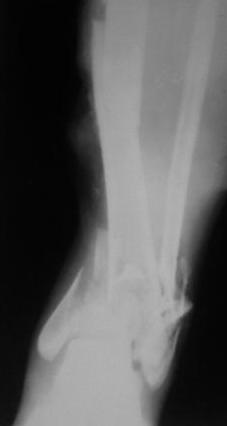

[Ortho] Открытый перелом 43.С3.3

Больной 41г переведен из ЦРБ, травма в  результате ДТП- 5 дней

назад, произведена ПХО  раны, наложена  гипсовая  повязка.

Об-но; начиная  с  с/з  голени  продольно - почти циркулярная рана, с

признаками инфицирования - покраснение, отечность, усиление  боли,

местная  т-ра и  мутные  кровянистые выделения из  раны, и

выраженная деформация голени. В отд нашей коллегой в  экстренном

порядке в  задней  поверхности голени щвы  распушены, выпушено около

50мл мутная  гематома, АВФ, умеренная дистракция, антибиотики, и т.д.

Наш план; после устранения воспалительных процессов, перемонтаж

аппарата, репозиция оставшихся смешений спицами с  упорной

плошадкой и  стабилизация аппарата, дальше  по  обстановке.